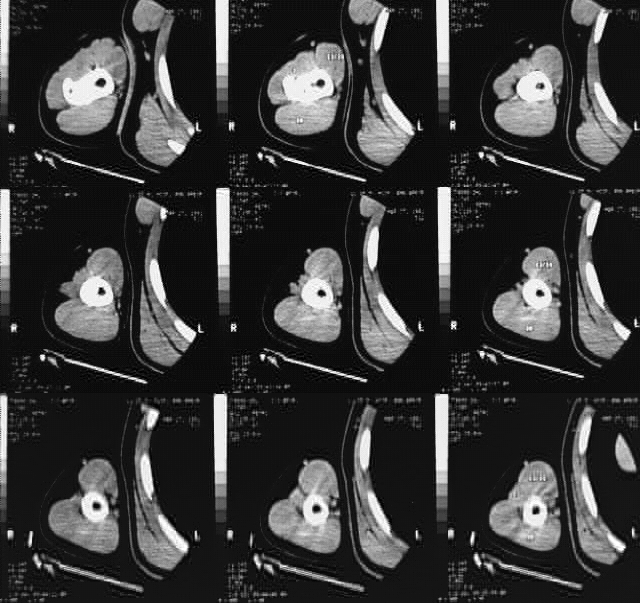

Upper Limbs:Upper Limb CT: